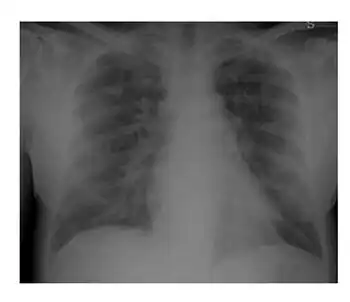

The syndrome is characterized by dyspnea, fever, weight gain, hypotension, and pulmonary infiltrates. This is effectively treated by giving dexamethasone and withholding ATRA (or arsenic trioxide) in severe cases. An elevated white count is sometimes associated with this syndrome, but is not always pathognomonic.